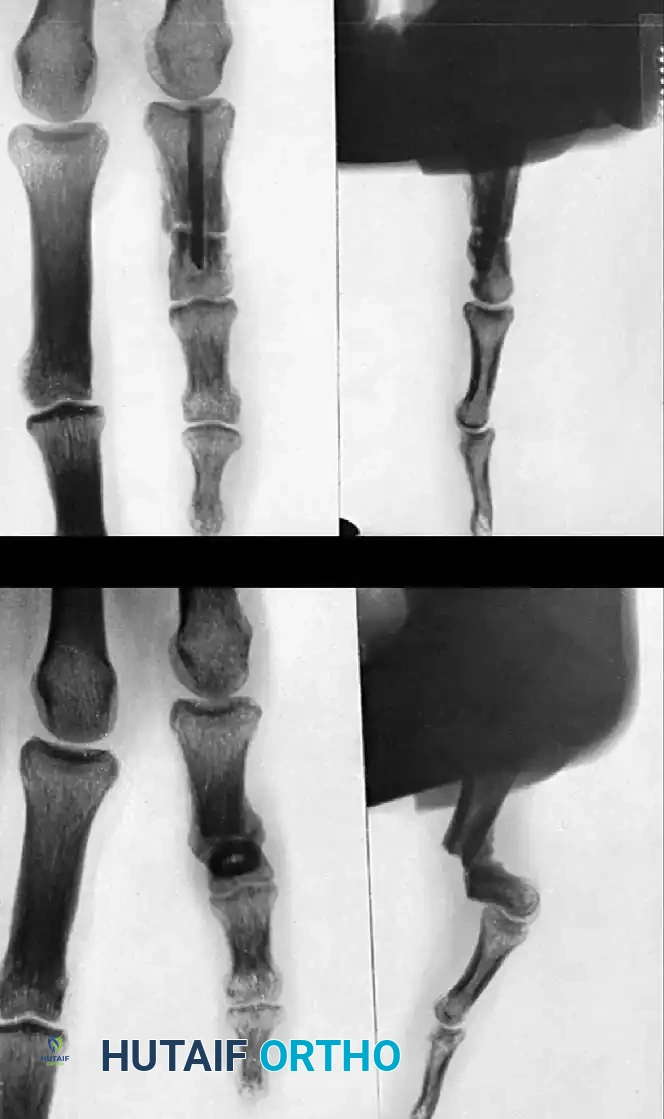

COMPLICATIONS OF HAND FRACTURES Surgical Diagram

Fig. 64-71 Malunited fracture of fifth metacarpal neck treated by open reduction and fixation with one Kirschner wire inserted obliquely. This rarely is necessary because normal motion of fifth carpometacarpal joint permits tolerance of 40 degrees of angulation at fracture site.

Phalangeal Malunion Correction

Malunion of a metacarpal shaft or of a phalanx can also be treated with a medullary cortical bone peg; however, the peg must be shaped meticulously to fit snugly without causing iatrogenic comminution.

Fig. 64-72 Malunion of a metacarpal shaft treated with a medullary cortical bone peg.